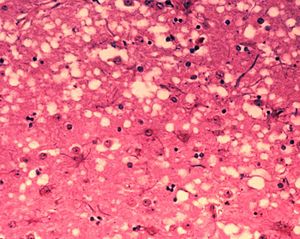

朊毒體

Prion

(直譯為普里昂、蛋白質侵染因子、毒朊、感染性蛋白質、普恩蛋白等),能引發哺乳動物的傳染性海綿狀腦病例如羊搔癢症TSE、瘋牛症 BSE、慢性消耗病 CWD,以及人類的克雅二氏病vCJD。它的獨特性是它不是生命體,結構上歸為蛋白質,但卻有傳染性,現行針對微生物的消毒殺菌方法都不能去除朊毒體,慢性及隱性傳播,檢測昂貴亦不普及,出現症狀亦無藥可救。只能以排除進入食物鏈作預防,因此活體屠前檢疫致為重要(雖然亦不能保証)。